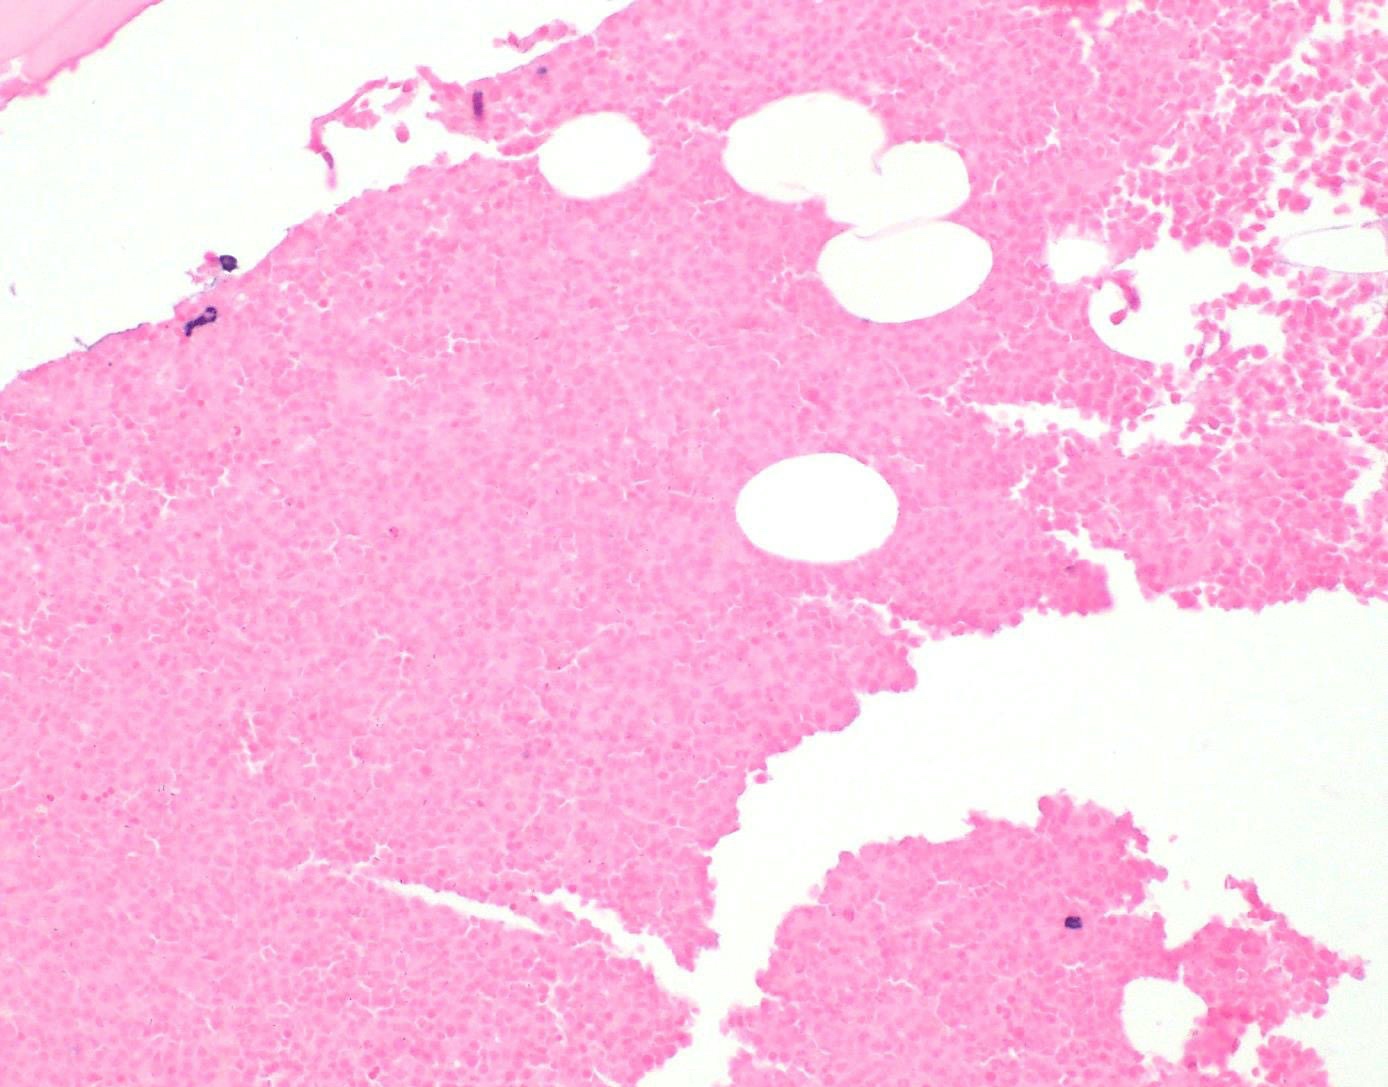

Microscopic (histologic) description

- Core biopsy (Am J Clin Path 1987;87:342):

- Interstitial clusters, nodules or sheets of plasma cells

- Areas of bone marrow may be spared with preserved hematopoiesis, other cases may have diffuse involvement and markedly suppressed hematopoiesis

- Prominent osteoclastic activity may be seen

- IHC to quantify plasma cells (CD138), stains for Ig kappa and lambda to establish clonality

Microscopic (histologic) images

Contributed by Genevieve M. Crane, M.D., Ph.D. and Tapan Bhavsar, M.D., Ph.D.